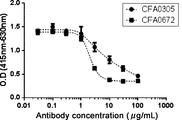

- Figure 9A illustrates inhibition of complement-activated liposome lysis by anti-C5 antibodies, as described in Example 5.1.

- Figure 9B illustrates inhibition of complement-activated liposome lysis by anti-C5 antibodies, as described in Example 5.1.

- the results of antibodies CFA0330 and CFA0341 grouped into epitope B, as described in Example 2.2, are shown.